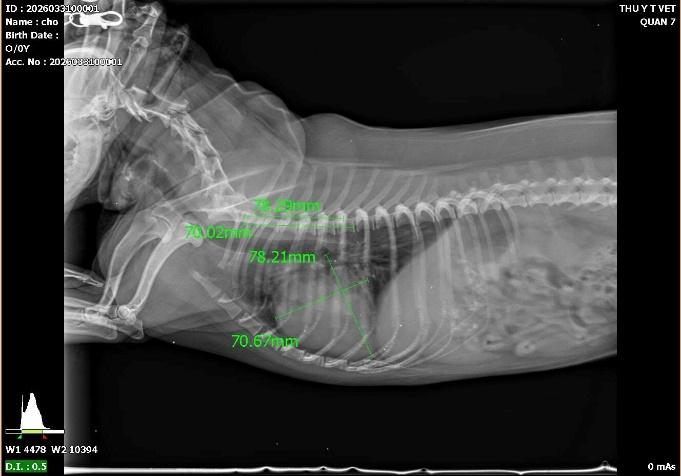

Không chỉ có siêu âm, X-quang cũng đóng vai trò trọng yếu trong việc tầm soát tim mạch. Tại Thú y T Vet Huỳnh Tấn Phát, chúng tôi thường sử dụng chỉ số VHS (Vertebral Heart Size) trên phim X-quang để đo lường kích thước tim so với cột sống.

Nếu tim có dấu hiệu to bất thường (Tim bò), hoặc bóng tim đè ép vào khí quản, đó có thể là dấu hiệu của bệnh suy tim, bệnh cơ tim giãn hoặc bệnh giun tim. Phát hiện sớm giúp thú cưng được sử dụng thuốc hỗ trợ tim mạch kịp thời, kéo dài tuổi thọ đáng kể.

.jpeg)

Hình ảnh: tim phì đại, và đo kích thước tim để xác định.